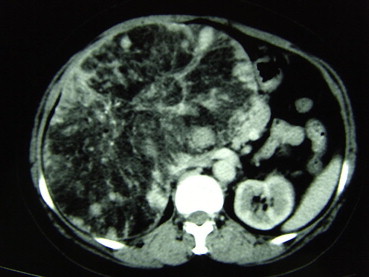

All patients had USG examination. Fifty-eight patients underwent both plain CT and intravenous contrast-enhanced CT examination (Fig. 1) and 35 patients underwent MRI examination (Fig. 2). After we analyzed our data, we were able to suggest the diagnostic features of hepatic angiomyolipoma (Table 2). Unfortunately, using these criteria, only 23% of patients with hepatic angiomyolipoma could be diagnosed before treatment.

CT showing peripheral angiomyomatous component with soft-tissue alternation, a ...

Figure 1.

CT showing peripheral angiomyomatous component with soft-tissue alternation, a fatty component and prominent central vessels.

● Plain CT scan - a heterogeneously low density mass with low attenuation value (< −20 HU)

● Contrast-enhanced CT scan - marked enhancement of the soft tissue components in the arterial phase and enhancement in the portal venous phase

Multiple modalities of tests have been used to aid in the diagnosis of hepatic angiomyolipoma. Laboratory tests, such as viral markers for hepatitis, tumor markers, and liver function, have been negative or have not been proven to be specific or helpful in the diagnosis of hepatic angiomyolipoma. Identification of fat within a liver lesion can be critical in characterization of the lesion. Radiographically, hepatic angiomyolipoma has the characteristic imaging features of fatty tissue, yet the diagnosis is only correctly suggested in a minority of cases. Although a combination of USG, CT, MRI is able to increase the accuracy in preoperative diagnosis, hepatic angiomyolipoma usually shows non-typical patterns in imaging studies.7; 8; 9 ;  10 The difficulty in imaging diagnosis occurs because of the wide variation in the proportions of vessels, muscles, and fatty tissue in different tumors. Consequently, hepatic angiomyolipoma is difficult to diagnose on imaging studies alone. USG is currently the first screening method for liver tumors, but USG findings of most liver tumors are nonspecific. As hyperechoic liver nodules cannot be characterized by USG, subsequent examination using CT, MRI, or even fine-needle aspiration cytology (FNAC) is necessary.18 CT, and MRI typically demonstrate the fat component and prominent central vessels. At CT scan, hepatic angiomyolipoma has been reported to consist of two parts: a peripheral angiomyomatous component with soft-tissue attenuation and a fatty component with an attenuation value less than –20 HU.5; 6; 7 ;  8 MRI characteristics vary, depending on the proportion of intratumoral fat. Frequently, hepatic angiomyolipoma has a high fat content, with high signal intensity on T1-weighted images and a significant drop in signal intensity on fat-suppressed images.5; 6; 7 ;  8 Diagnosis using FNAC or biopsy is again difficult, because of the heterogeneity of the lesion. The smooth muscle cells are the only specific and diagnostic components of hepatic angiomyolipoma and are characteristically immunostained positive for HMB-45 and Melan-A. This portion of tissue may or may not be sampled. The definitive diagnostic tool remains the histopathologic examination of the surgically resected specimen, coupled with immunohistochemical staining.